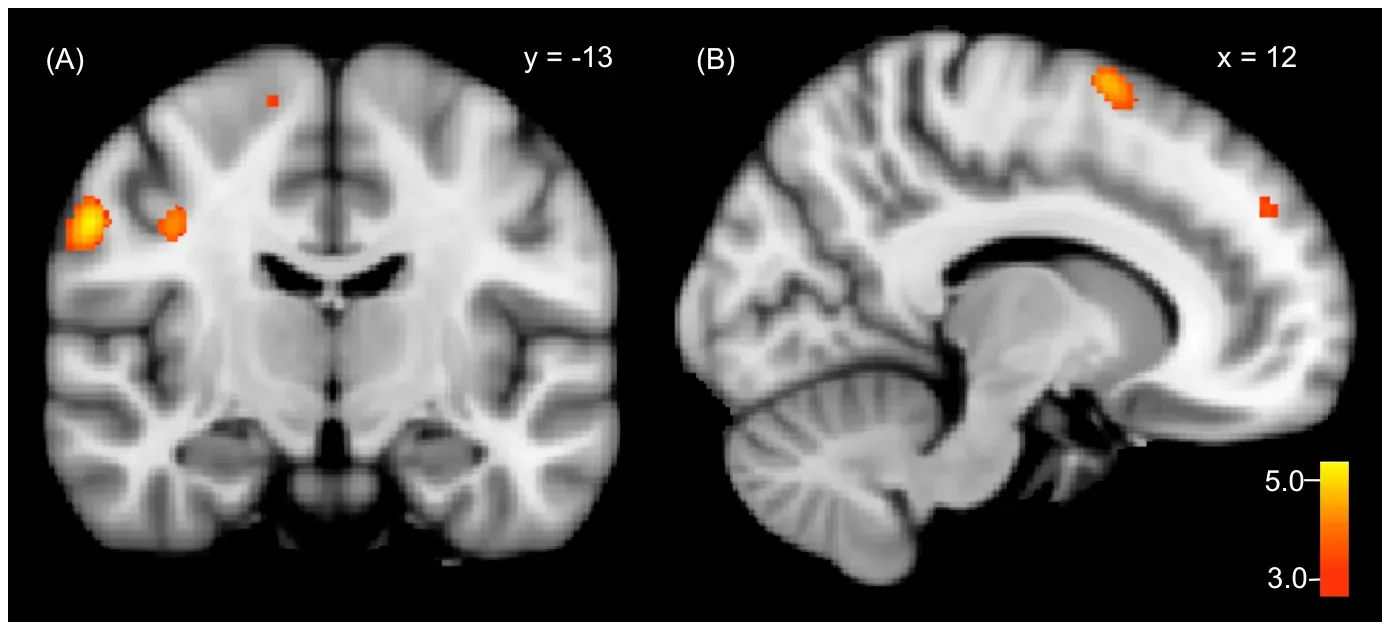

Brain imaging studies show that laughter lights up a surprisingly ancient set of neural circuits, including areas involved in emotion, movement, and reward. When we laugh, the brainstem coordinates the breathing patterns, the limbic system helps shape the emotional tone, and reward centers release feel-good chemicals that reinforce the behavior. This layered architecture suggests that laughter evolved first as a basic vocal signal and then was gradually woven into more complex social and cognitive systems. In other words, your brain does not just find something funny and then tack laughter on top – laughter is built in at multiple levels.

Different regions of the brain play distinct roles in this process. The frontal lobes help interpret context and detect incongruity, while temporal areas process language and social cues. The motor cortex and brainstem, meanwhile, coordinate the complex muscle patterns needed for the characteristic vocal bursts and facial expressions. When scientists electrically stimulate certain regions in awake patients during surgery, some people report an urge to laugh or smile, while others interpret neutral situations as suddenly funny. That strange finding underscores how much our sense of humor depends on invisible neural tuning, not just on the content of a joke.